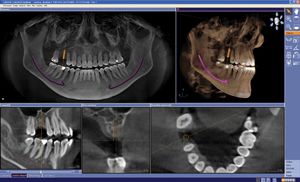

3D digital x-ray technology at the Orange County practice of Dr. Andrew Mortensen enables us to deliver diagnoses and treatment that are more accurate and efficient. Our cone-beam computed tomography (CBCT) system gives us a high-resolution view of the areas in the jaw and face that are not visible to the naked eye, but are crucial to your oral health.

- Improved analysis and treatment planning: These images can be enlarged, enhanced, rotated 360 degrees and adjusted for optimal contrast. This level of accuracy is especially beneficial during the planning phase of dental implant surgery. It is extremely important that implants be placed in an area of the jaw with adequate bone mass, where nerves, blood vessels, and sinus cavities will not be disturbed.

During treatment, a patient's head is positioned between two sides of a horseshoe-shaped scanner. The scanner rotates in a complete circle around the head, using a cone-shaped x-ray beam to capture data. That data is then used to create a 3D image of the teeth, jaw, sinuses and jaw joints.